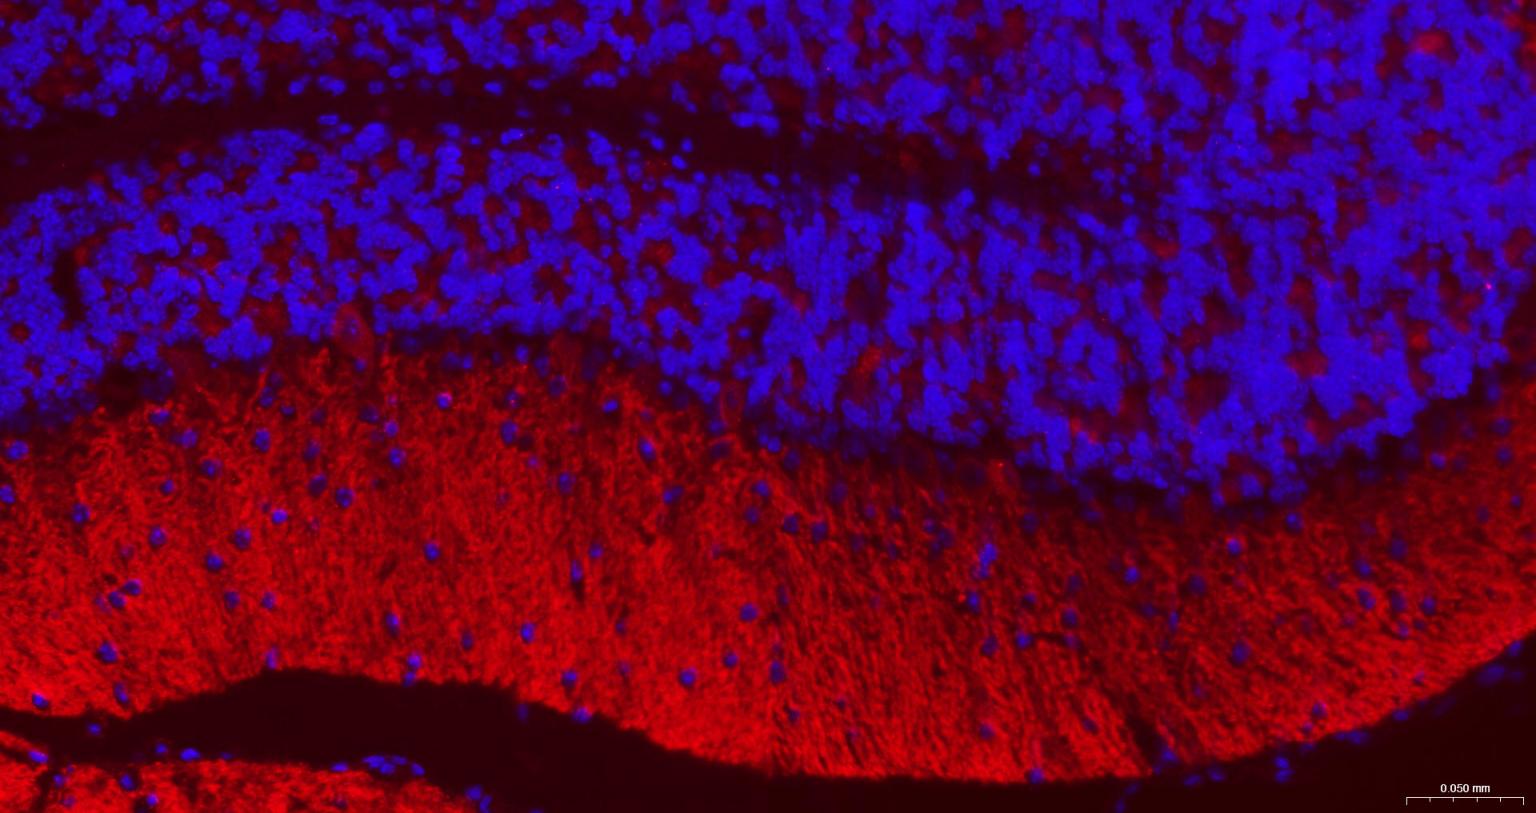

Paraformaldehyde-fixed, paraffin embedded Mouse Cerebellum; Antigen retrieval by boiling in sodium citrate buffer (pH6.0) for 15 min; The section was incubated with GABBR2 Monoclonal Antibody, Unconjugated (bsm-54237R) at 1:200 overnight at 4°C. Followed by conjugated Goat Anti-Rabbit IgG antibody (Red, bs-0295G-BF594), DAPI (blue, C02-04002) was used to stain the cell nuclei.

Paraformaldehyde-fixed, paraffin embedded Rat Cerebellum; Antigen retrieval by boiling in sodium citrate buffer (pH6.0) for 15 min; The section was incubated with GABBR2 Monoclonal Antibody, Unconjugated (bsm-54237R) at 1:200 overnight at 4°C. Followed by conjugated Goat Anti-Rabbit IgG antibody (Red, bs-0295G-BF594), DAPI (blue, C02-04002) was used to stain the cell nuclei.